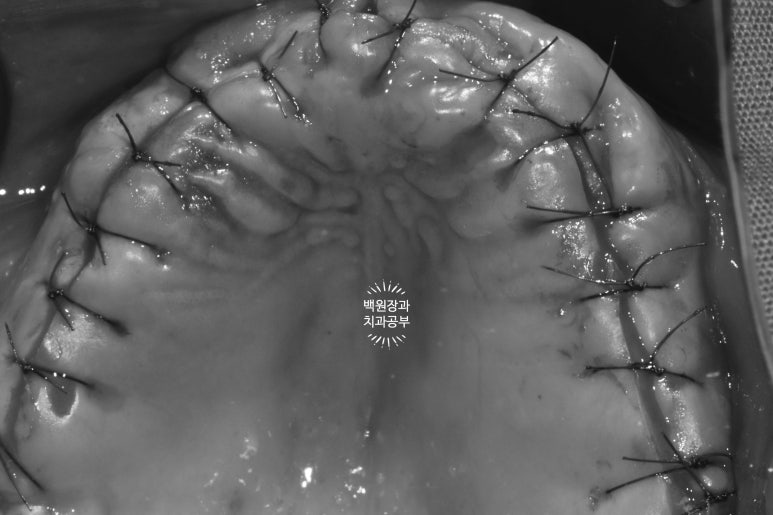

최선을 다해 열심히 수술을 하고나서 해야하는 것은..

최대한 예쁘게 꿰매드리고 기도하는 것입니다.

기도메타.... 환자분의 훌륭한 치유능력은 곧 저에게 복이죠.

일주일이 지난 시점에서, 크게 벌어지지 않고 상당히 잘 아물고 있는 잇몸 상탤르 확인할 수 있었습니다.

다소 붓기가 있어 잇몸뼈가 뚱뚱해 보이는 것은 당연하긴 하나, 한편으로 넉넉한 뼈이식을 해두었기 때문이기도 할 것입니다.

열심히 예쁘게 꿰매드리고 나서 .. (생각보다 너무 깔끔하잖아..?)

보면 뼈이식이 많이 된 것 같지 않나요?

상당히 볼쪽으로 뚱뚱해진 잇몸뼈를 보실 수 있을겁니다.

유독 앞니의 뼈가 얇아 더 많이 뼈이식을 했던 기억이 납니다.